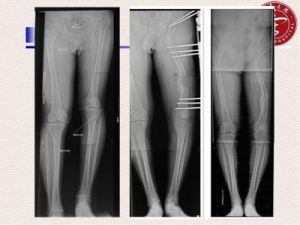

治療

1、西醫多採用做關節松解術,成功率很低,且費用昂貴,病人痛苦大,目前在世界上是一種不成熟的手術。